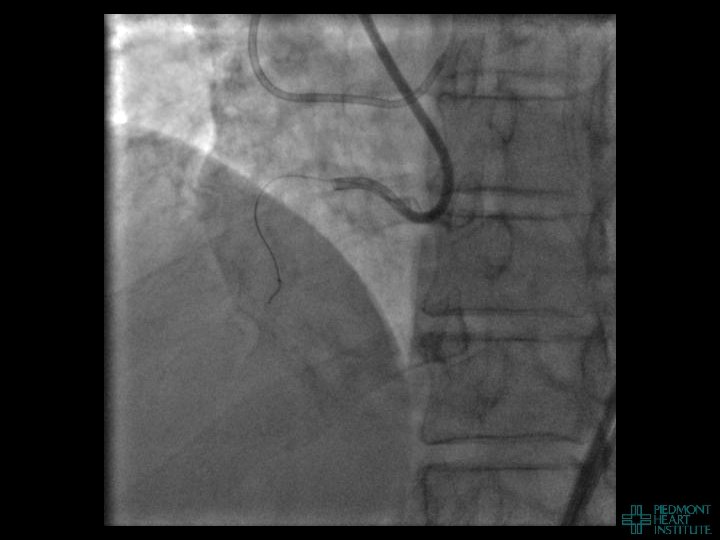

Coronary Perforation Methods of Patient Management • Dual Catheter (‘Ping Pong’) Technique • Prolonged

Coronary Perforation Methods of Patient Management • Dual Catheter (‘Ping Pong’) Technique • Prolonged balloon inflation and covered stents • Reversal of anticoagulation — Know contradictions to protamine sulfate for UFH; Avoid bivalirudin, LMWH — Reserve GP 2 b 3 a inhibition until successful crossing and wire change-out Embolization • — Coil, gelfoam, methacrylate, autologous blood/fat • Microcatheter Occlusion • Confirmation of successful management — Contralateral injection — Right heart catheterization — Echocardiogram — Contrast echocardiography